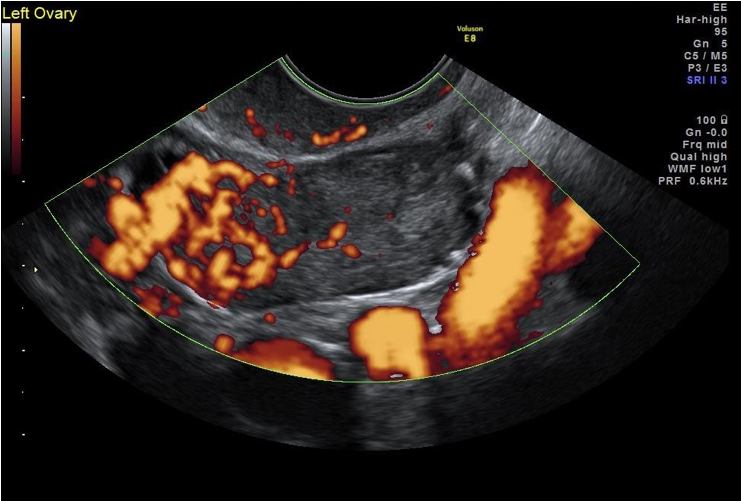

Förekommer hos kvinnor i alla åldrar, ger ofta endokrina symptom. I en serie på 23 patienter fann man att tumören var helt solid i 60 % av fallen och innehöll en solid komponent i 96 % av fallen 5. De flesta tumörerna är ensidiga, solida eller har solida komponenter som är måttligt till rikligt vaskulariserade. Leydigcell tumörer är ofta små solida tumörer (1-3cm), (Bild 8), Sertolicelltumörer är också solida men kan vara något större (4-7cm), medan Sertoli-Leydigcelltumörer är antingen solida små till mellanstora (3-7 cm eller flerrummiga till solida med ett stort antal hålrum och solida partier.

Bild 8. Leydig celltumör hos 73 årig kvinna med ökad libido, klitoris hypertrofi och viriliserade symptom. Notera liten välvaskulariserad tumör